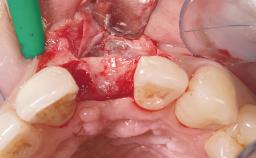

A 39-year-old male patient presented with a chief complaint of discomfort and gingival discoloration around his maxillary left central incisor. He was in good general health and was a non-smoker. His past dental history was significant because of the traumatic fracture of tooth 21 in a sporting accident at age 13. Initial dental treatment included endodontic therapy and a full-coverage restoration. The patient became symptomatic 5 years later, when structural failure of the tooth resulted in the dislodgment of the crown. Endodontic retreatment, apical surgery, and post-and-core restoration were performed.

Bone Augmentation Horizontal|Staged

Augmentation Materials Xenogenous|Membrane

Bone Volume Deficient horizontally, requiring prior grafting